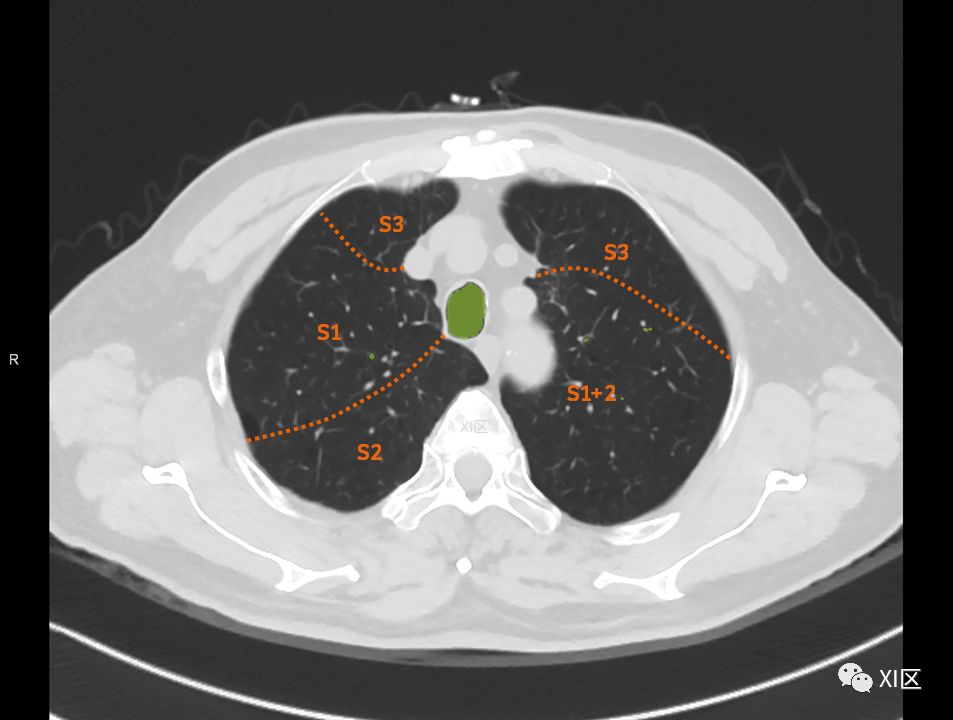

在进行肺的分段时,可以上下观察浏览,沿着相应气管的走形可以更容易准确地进行分段。

肺的断层分段示意图